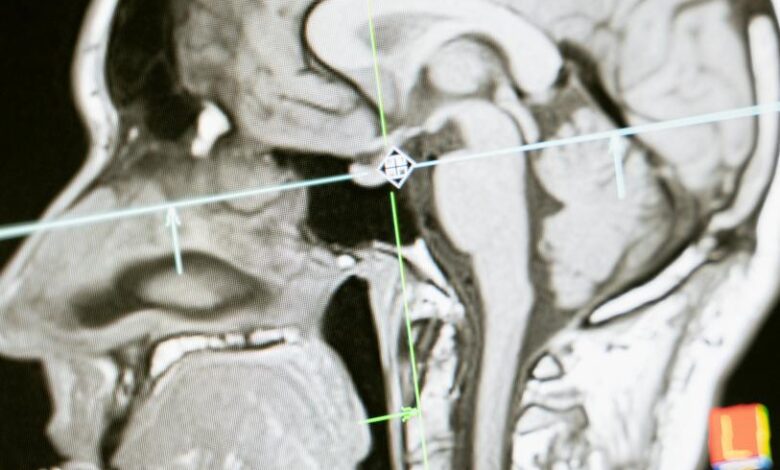

Estudios de imagen que descarten hemorragia